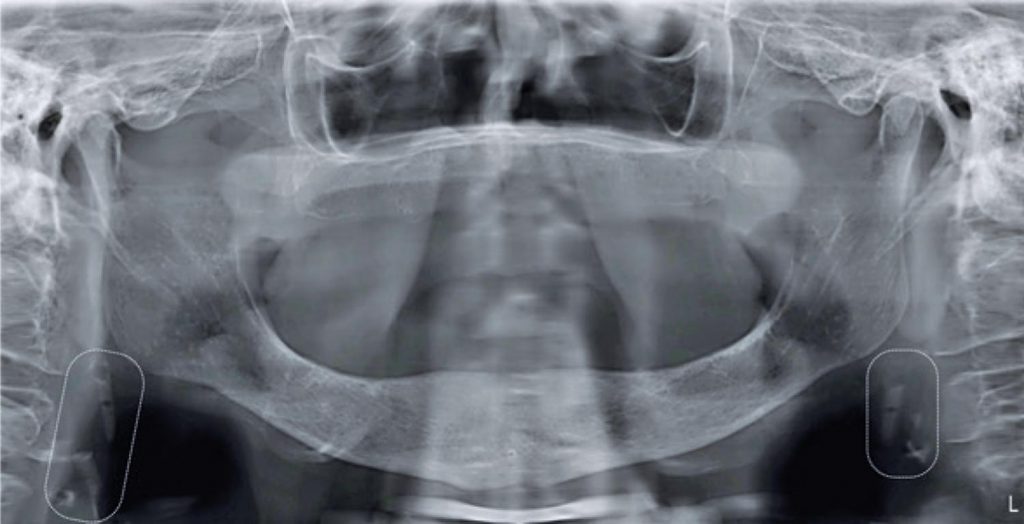

Carotid artery atherosclerosis is one of the main causes of stroke.() In dental panoramic radiography (DPR), radiopaque images adjacent to cervical spine can be an indicative of calcification in bifurcation of carotid artery. Such calcifications can represent calcified atheroma plaques,() which diagnosis is confirmed by the Doppler ultrasonography.(,)

Dentists can identify these areas through DPR and differentiate them from radiopacities that can be observed in the carotid region. The identification of these area and referral of these patients to specialized medical evaluation may contribute to stroke prevention.(,,)